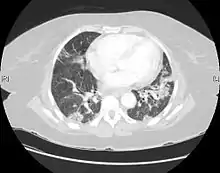

| CT scan of a patient with UIP. There is interstitial thickening, architectural distortion, honeycombing and bronchiectasis. | |

UIP may be diagnosed by a radiologist using computed tomography (CT) scan of the chest, or by a pathologist using tissue obtained by a lung biopsy.

Radiologically, the main feature required for a confident diagnosis of UIP is honeycomb change in the periphery and the lower portions (bases) of the lungs.[3]